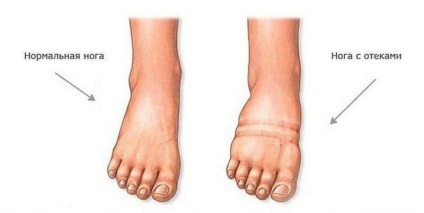

Folyadékretenciót gyakoribb a vesebetegségben szenvedők, de ez is beszélni a problémákat, a májat.

Gyakran nyilvánul formájában duzzadási lábak és más testrészeket. Könnyen azonosítható, szorosan nyomni egy ujjal a bőrt, majd elengedi. Ha az ujjlenyomat néhány másodpercig, van duzzanat.